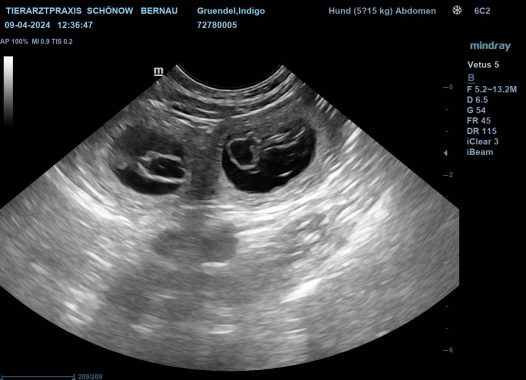

Heute war ich mit Indigo beim Ultraschall und es ist bestätigt worden, Indigo erwartet Welpen. Soviele Bewerber haben Interesse an einem Indigo-Puppy, teilweise warten sie schon 2 Jahre. Leider wird es ein kleiner Wurf werden, aber ich freue mich riesig denn ich habe schon nicht mehr daran geglaubt.